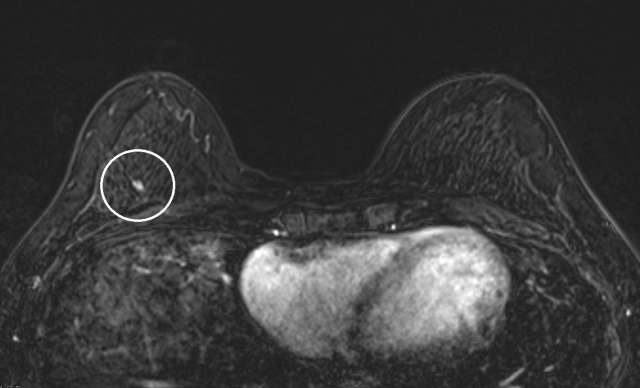

Case: Atypical Ductal Hyperplasia Figure 3

Case 3: Axial T1 subtraction of the first pass demonstrates focal non-mass enhancement in the right breast at 12 o’clock, 5 centimeters from the nipple, posterior depth, measuring 7mm and with fast persistent kinetics (not shown). Pathology demonstrated atypical ductal hyperplasia.